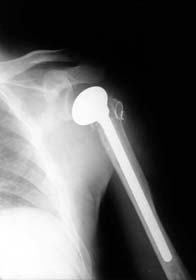

骨性关节炎造成的肩关节软骨破坏,骨刺形成 肱骨头粉碎骨折

全肩关节置换术后示意图 肱骨头置换后X线片